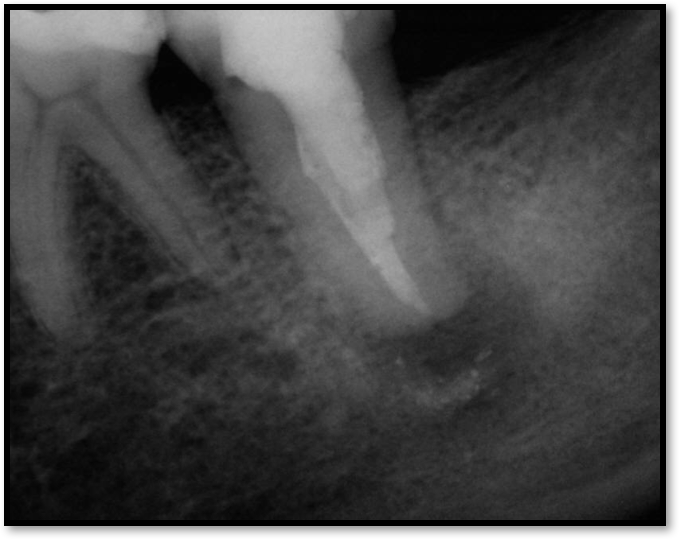

Figure 6 shows the successful root canal that stopped the patient from being in pain, but she still had some discomfort. The images did not show anything significant; the case was completed at a time when cone-beam computed tomography (CBCT) was not routine. The clinicians had to trust what they saw, which was 6-mm probing that left a chance for a crack in the tooth. There was a buccal fracture of the mesial root. There was bone apical to it but nothing coronally, so they decided to resect the root. They cut it out, put some holes into the bone, and added demineralized freeze-dried bone. They also later put a collagen membrane over it and closed it.

Fig 5. Root tip left from old extraction.

Figure 5